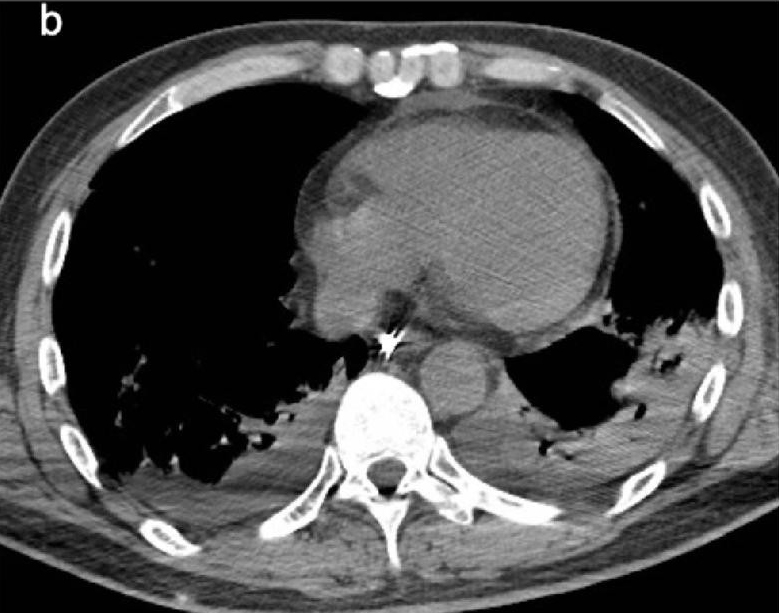

Sono immagini scioccanti quelle diffuse dai ricercatori dell'Istituto Nazionale per le Malattie Infettive Lazzaro Spallanzani di Roma in uno studio in via di pubblicazione sull'International Journal of Infectious Diseases. Sono le radiografie e le immagini della TAC dei polmoni appartenenti alle prime due persone risultate infette in Italia, due turisti cinesi in vacanza, e che dimostrano quanto può essere devastante il nuovo coronavirus.

I due pazienti, un uomo di 67 anni e una donna di 66, erano in forma e in salute. Seguivano solo una terapia orale per tenere a bada l'ipertensione. Dopo aver riscontrato problemi respiratori e febbre, la coppia è stata sottoposta a test di laboratorio che hanno confermato l'infezione con il virus SARS-CoV-2. Entrambi i pazienti hanno continuato ad aggravarsi fino a sviluppare la Sindrome da Distress Respiratorio Acuto (ARDS - Acute Respiratory Distress Syndrome).

Ci sono voluti solo quattro giorni per arrivare all'insufficienza respiratoria e due giorni dopo entrambi i pazienti respiravano solo grazie a un ventilatore. Le prime radiografie effettuate sui pazienti mostrano “opacità del vetro smerigliato”.

Lo studio ha anche scoperto che i vasi sanguigni che trasportano il sangue dal cuore ai polmoni per ossigenarsi si stavano allargando. Questa condizione, nota come ipertrofia, riduce lo spazio per l'aria, causando difficoltà respiratorie. È probabile che questo segno sia correlato all'iperemia - eccesso di sangue nei vasi polmonari - causato dall'infezione virale.

«I modelli polmonari in entrambi i pazienti sono caratterizzati da ipertrofia dei vasi polmonari, che sono aumentati di dimensioni, in particolare nelle aree con danno interstiziale più pronunciato», spiegano i ricercatori.